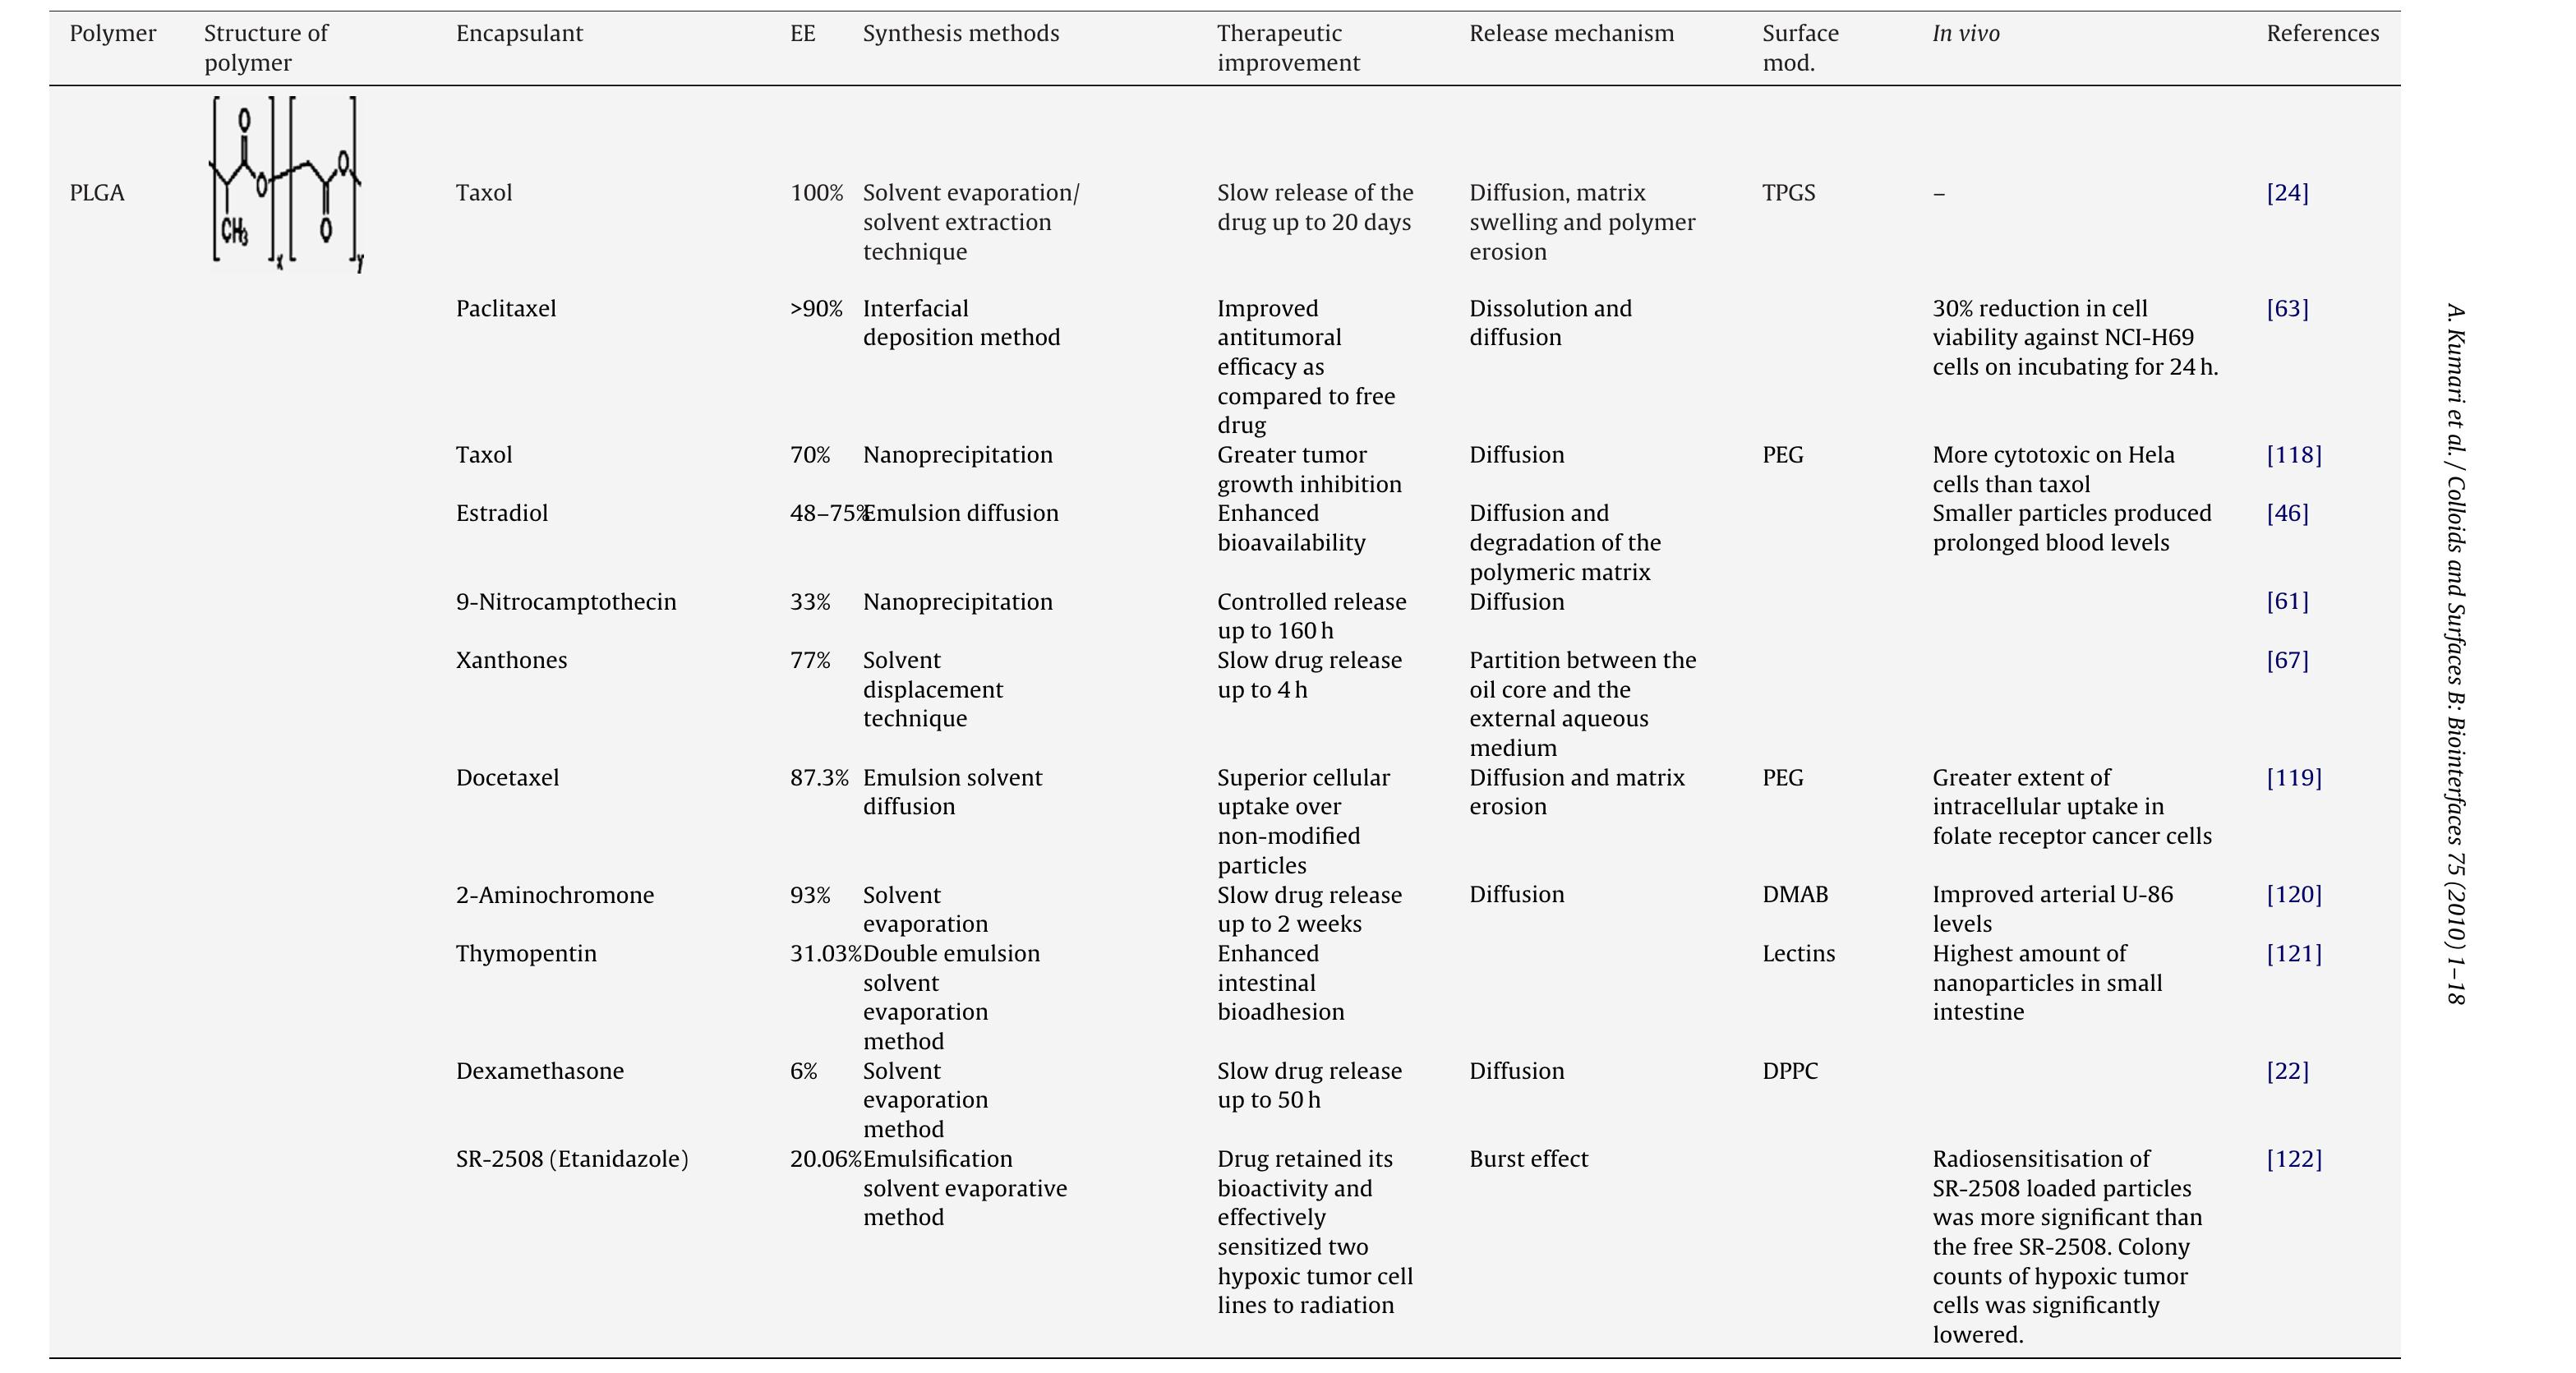

Poly(lactic-co-glycolic acid) (PLGA) is one of the most successfully developed biodegradable polymers. Among the different polymers developed to formulate polymeric nanoparticles, PLGA has attracted considerable attention due to its... more

The architecture of an engineered tissue substitute plays an important role in modulating tissue growth. A novel poly(D,L-lactide-co-glycolide) (PLGA) structure with a unique architecture produced by an electrospinning process has been... more